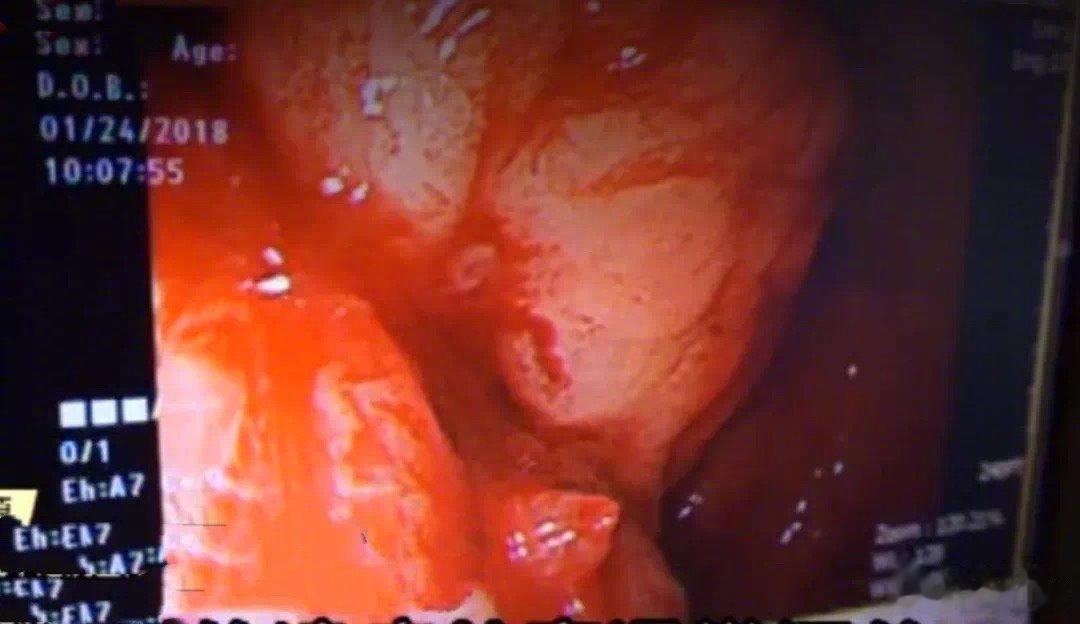

吃药时很多人都有的这种习惯,其实很危险!2018年1月23,某位男大学生因为感冒